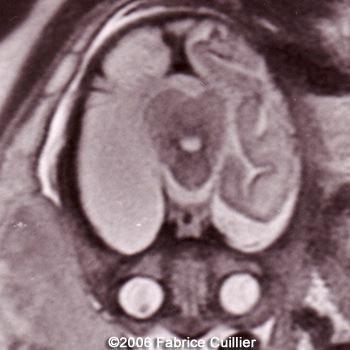

The following images are obtained in a 3rd trimester fetus:

The final diagnosis was: Arachnoid cyst